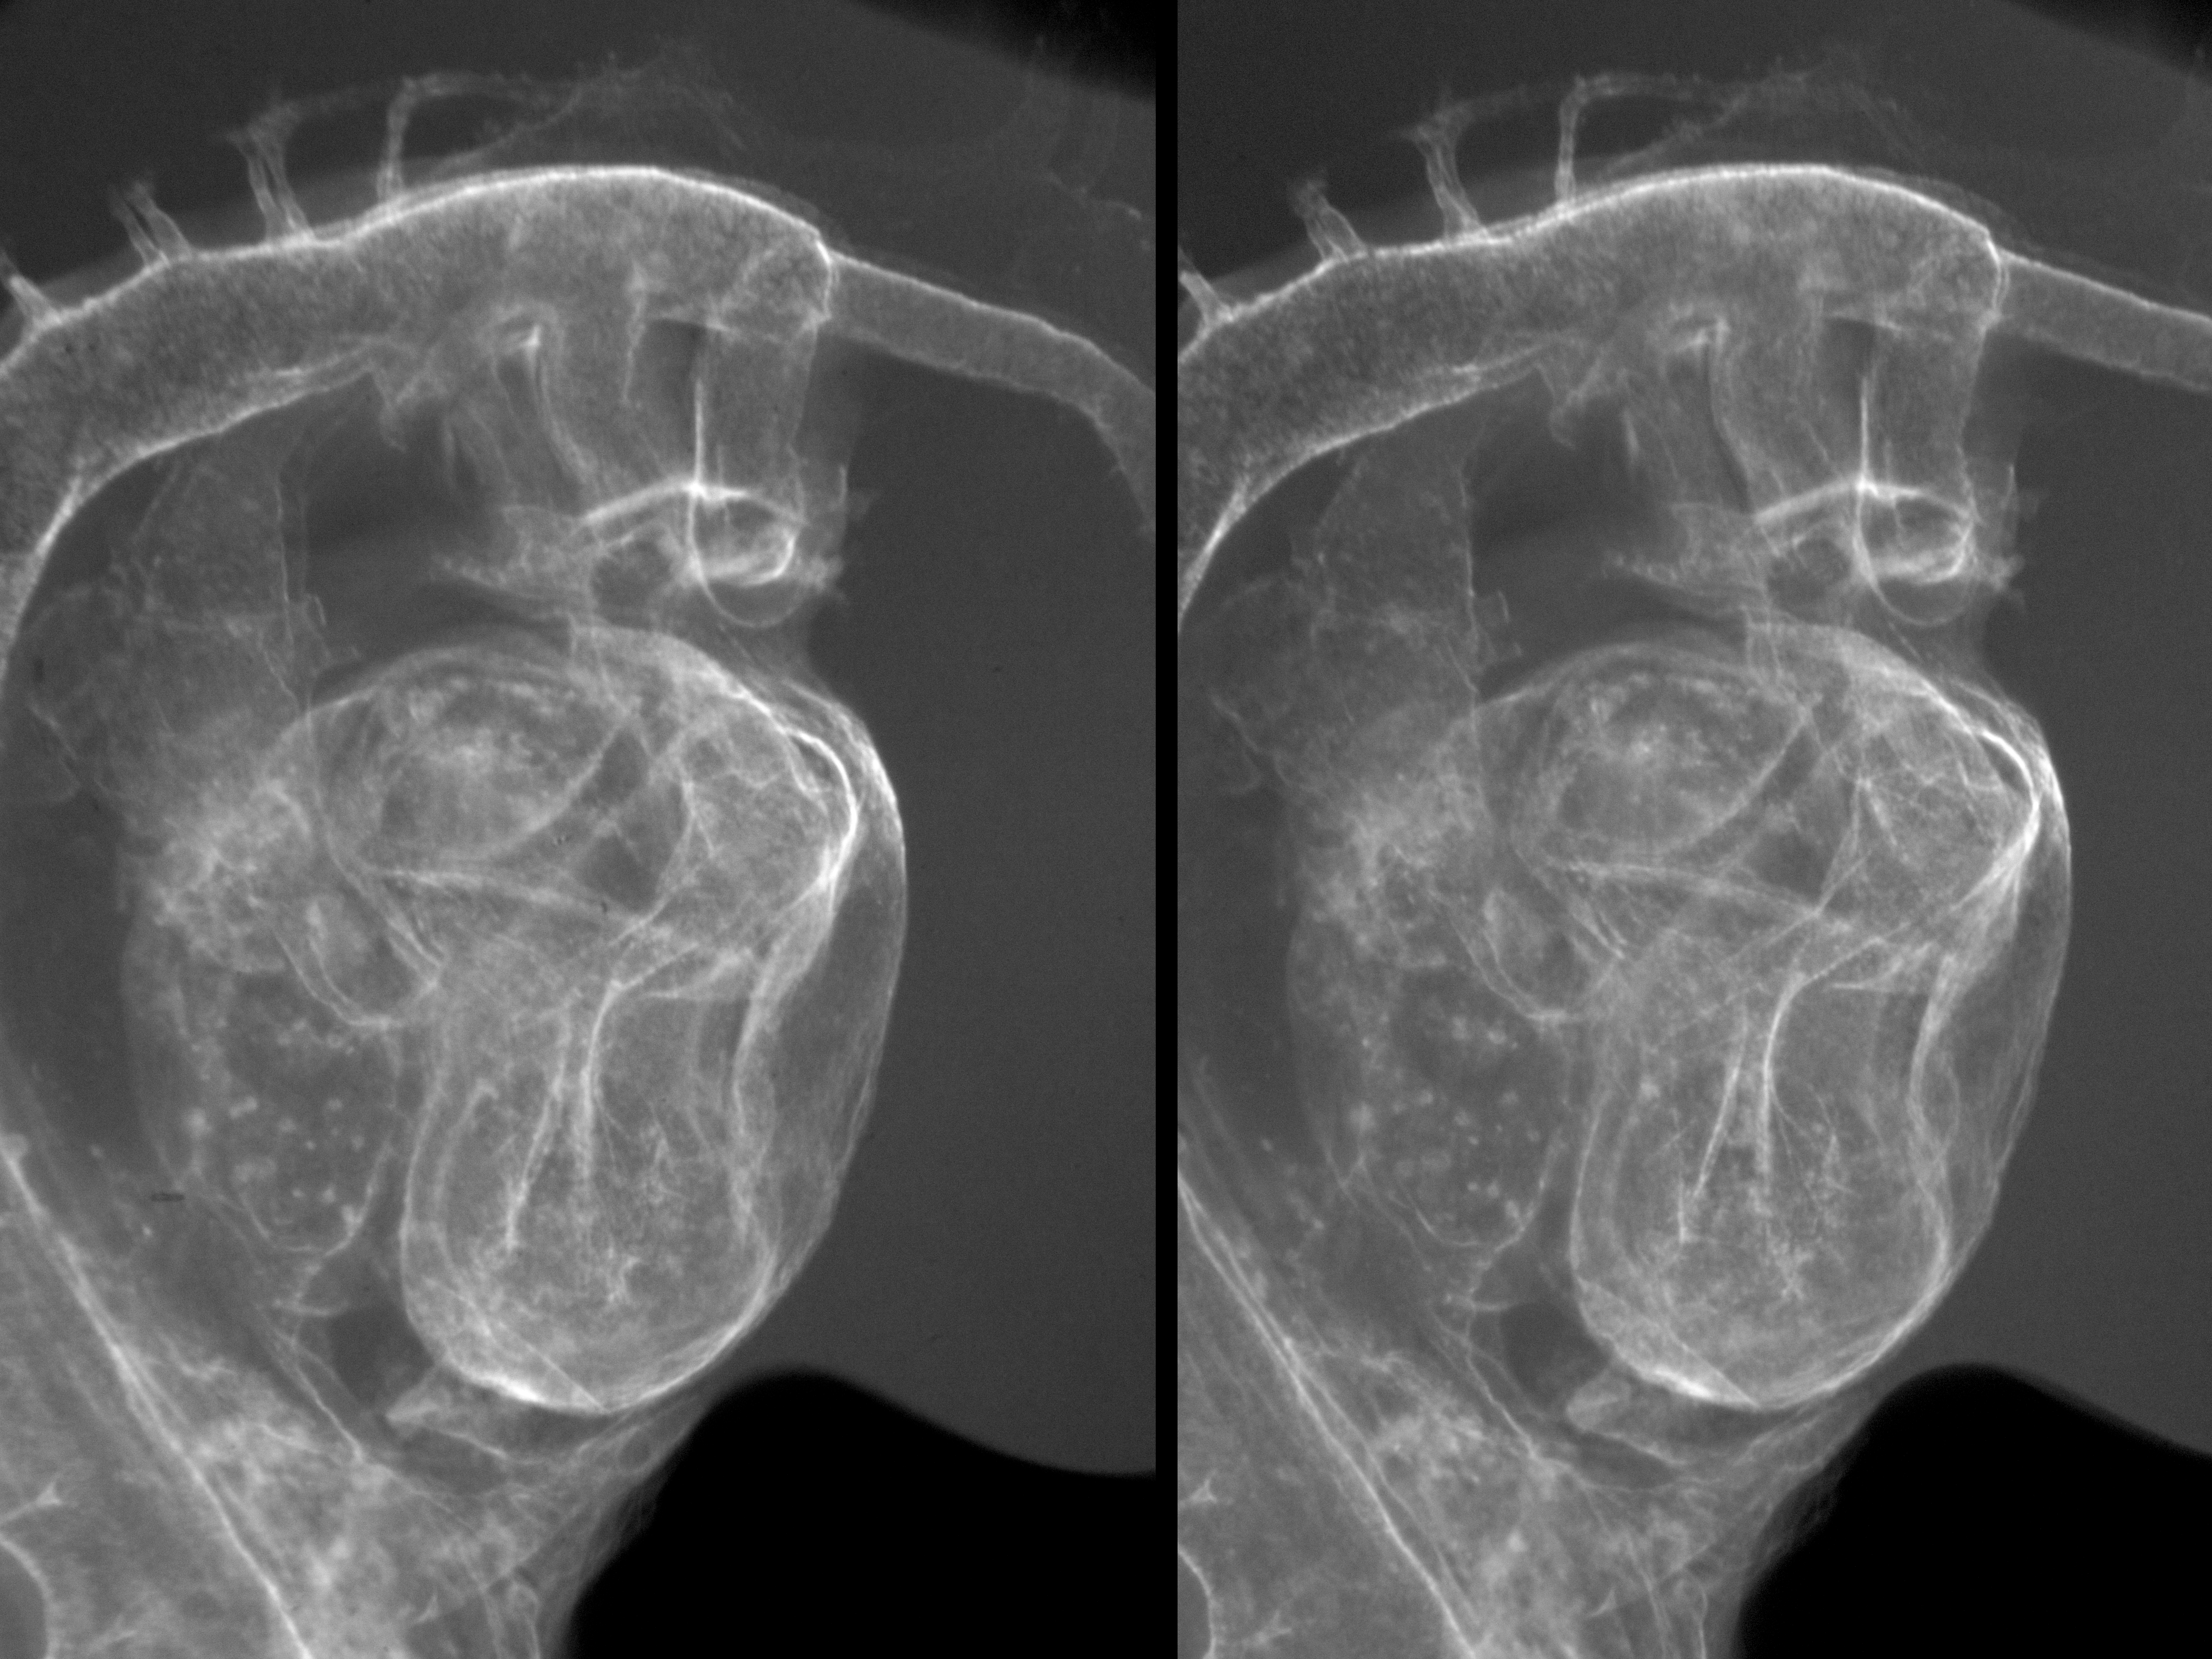

Chick Embryo Microangiography

Hamburger-Hamilton (HH) Stage 18 (approx. 3 days)

Stereo X-Ray Micrographs